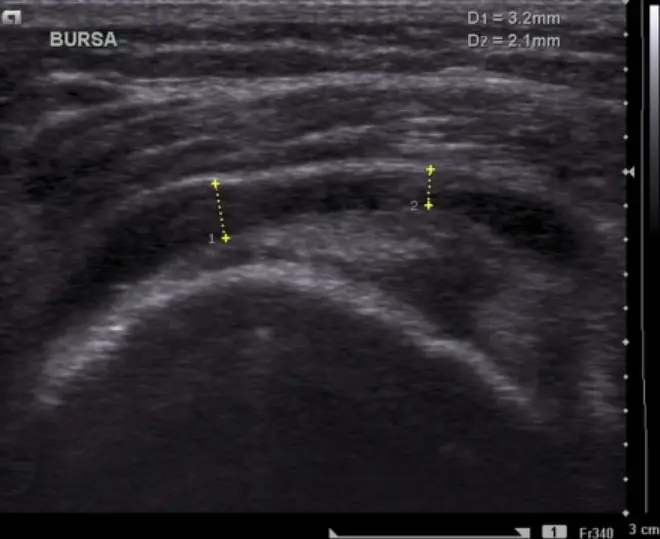

Musculoskeletal Ultrasound

Ultrasound allows us to visualize:

- Bursa fluid accumulation

- Tendon degeneration

- Calcifications

- Micro-tears

- Dynamic movement patterns

This helps distinguish:

- True isolated bursitis

- Tendinopathy with reactive bursitis

- Structural impingement

Ultrasound-guided diagnostics improve precision.